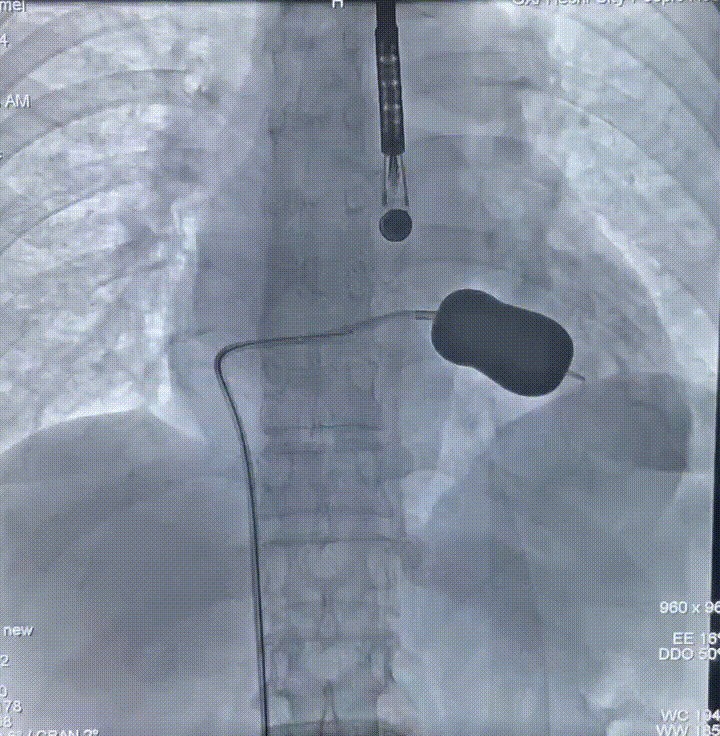

CT测量

主动脉根部CT

瓣环平均直径:

22mm

左室流出道平均直径:

23.3mm

窦宽:32/30/31mm

横位心:48°

左冠开口高度:

13.5mm

右冠开口高度:

10mm